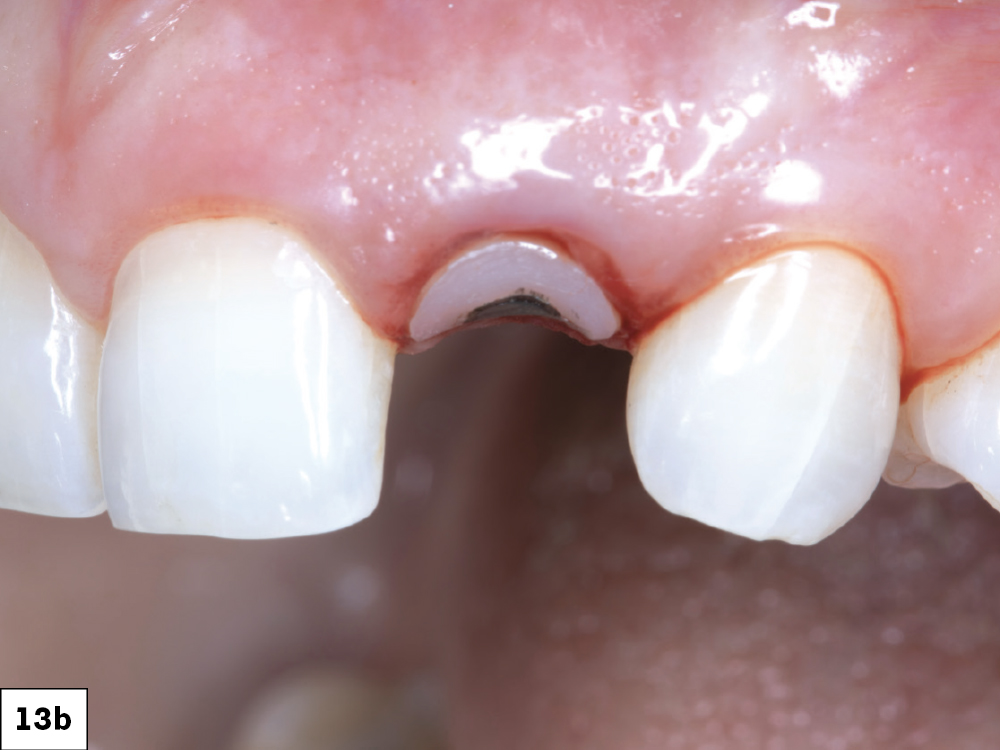

Figures 13a, 13b: The emergence profile created by the custom healing abutment is crucial for maintaining the gingival architecture, ensuring proper alignment of the papilla, margins, and soft tissue. The healing abutment helps retain the patient’s natural tooth appearance as closely as possible throughout the healing process.